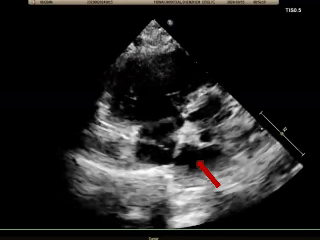

术后1周随访

超声报告:(1)房间隔封堵器位置正常,各瓣叶形态活动未见异常,右心比例稍大,左房室腔不大,心包腔内未见液性暗区; (2)多普勒检查:房水平未见残余分流;心功能:室壁运动协调,未见节段性异常;(3)先天性心脏病房间隔缺损封堵术后未见残余分流。